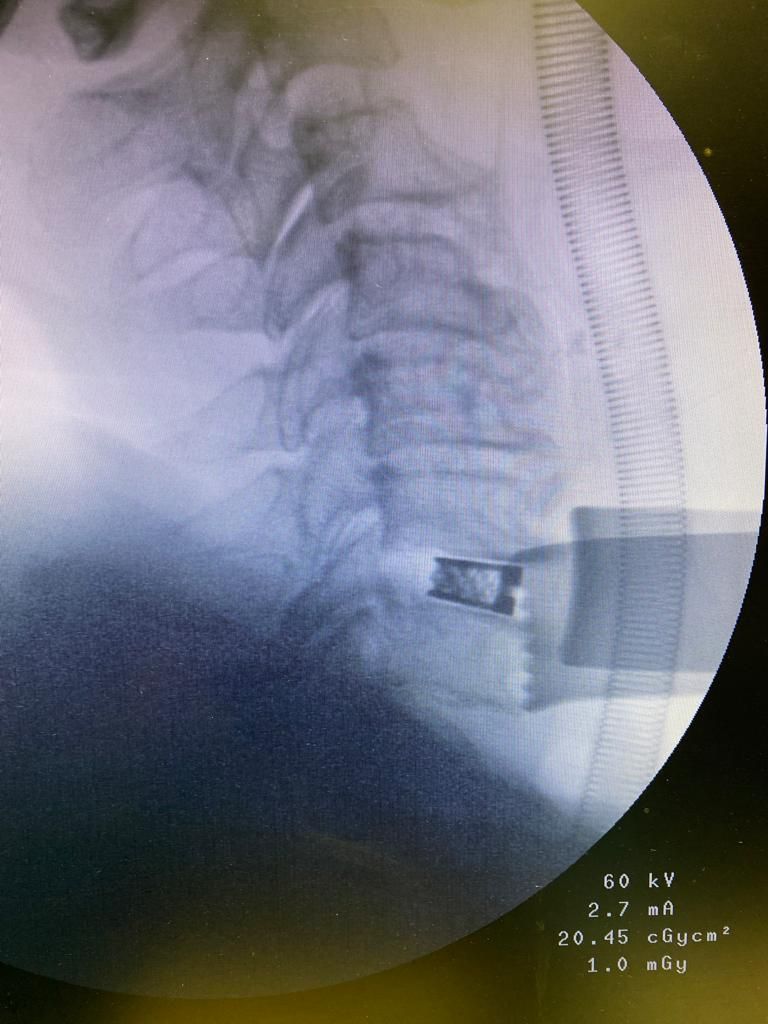

Nelle foto si può vedere un intervento di asportazione di ernia cervicale che ha causato nella paziente una perdita di forza della mano fortemente debilitante. L'intervento è stato eseguito presso il centro chirurgico toscano in convenzione con il sistema sanitario nazionale. La paziente sta gradualmente migliorando anche grazie alla fisioterapia. La scelta di un intervento chirurgico equivale ad intraprendere di un percorso che inizia dalla prima visita ambulatoriale e che prosegue con i successivi follow up. Lungo questo percorso il chirurgo e il paziente camminano insieme affrontando le stancanti salite e le successive discese per raggiungere gli obiettivi fissati nel primo incontro.